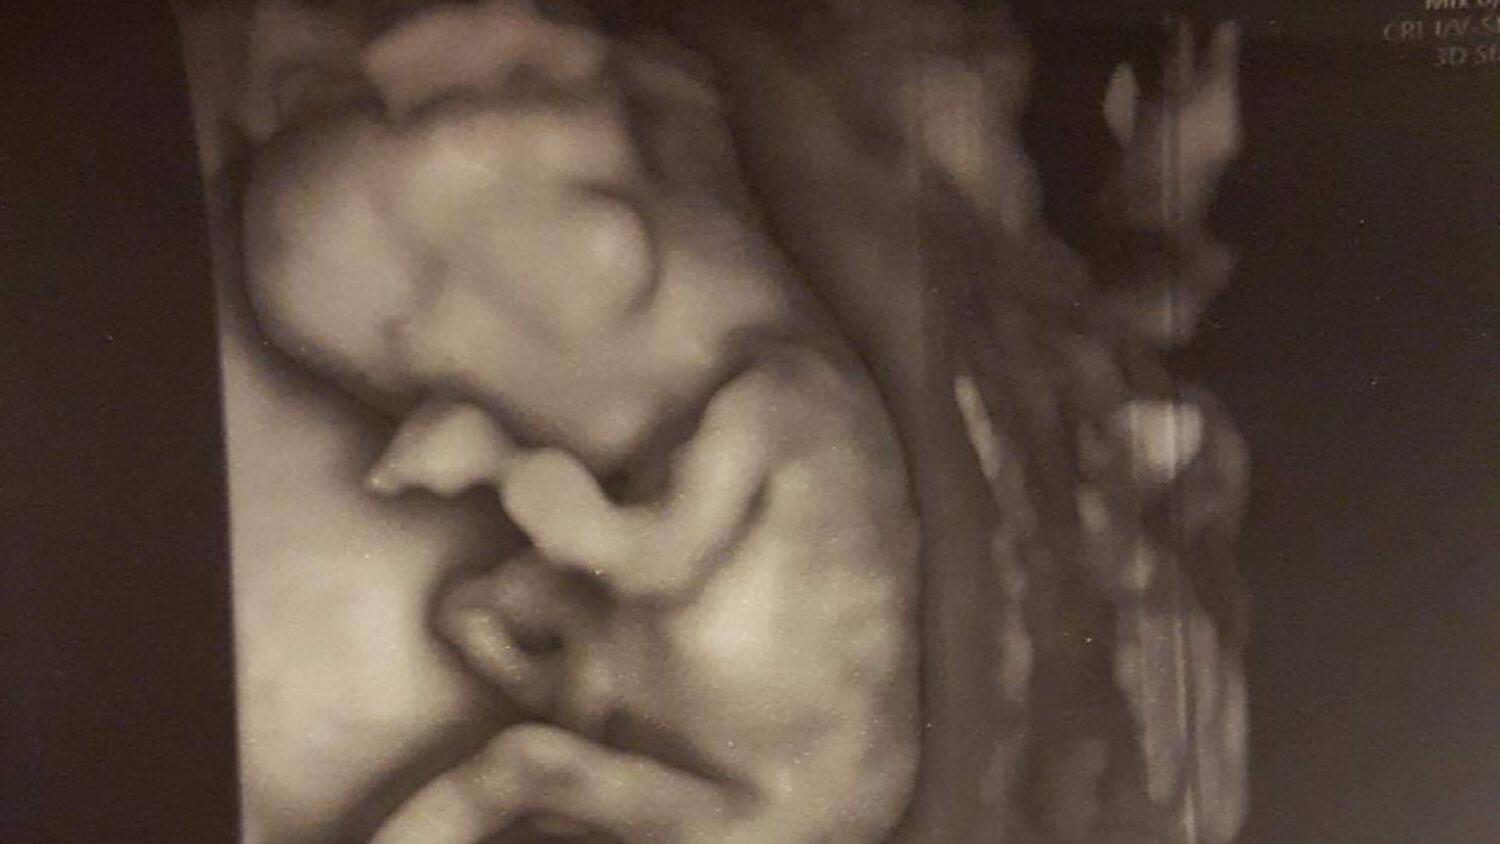

Keď som chodila každý týždeň na ultrazvuk, veľmi som sa tešila na našu malú – ako ju uvidím, akú má krásnu tvár, ako bojuje o svoj život, ako jej bije srdiečko, ako sa usmieva a ako si v brušku spokojne „pláva“. Tým mi vždy dávala najavo, že to spolu zvládneme, nech sa stane čokoľvek.

Raz, keď sa ma lekár na ultrazvuku znova opýtal, či nechcem ukončiť tehotenstvo, pozrela som sa na malú a povedala som: „Ja som predsa jej mama, pán doktor, kto iný by ju mal milovať, ak nie jej mama? Naše choré dieťa chce, aby som mu dala len lásku a milovala ho, nie aby som ho zabila preto, lebo je choré. Pre mňa je krásna a dokonalá presne taká, aká je. Presne taká, akú nám ju Pán Boh daroval.“